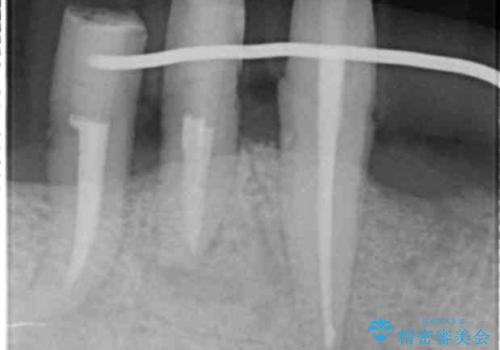

歯周組織検査・X線写真検査の結果、重度歯周病であることがわかりました。

残すことのできない歯を抜去し、入れ歯になることを回避すべくブリッジ治療を行いますが支台となる歯の歯周病を改善すべく歯周病により溶けた歯槽骨の再生治療を計画します。

再生治療により良好な歯槽骨の再生が得られ、入れ歯ではなく取り外しの必要のないブリッジによる機能回復を行うことができました。